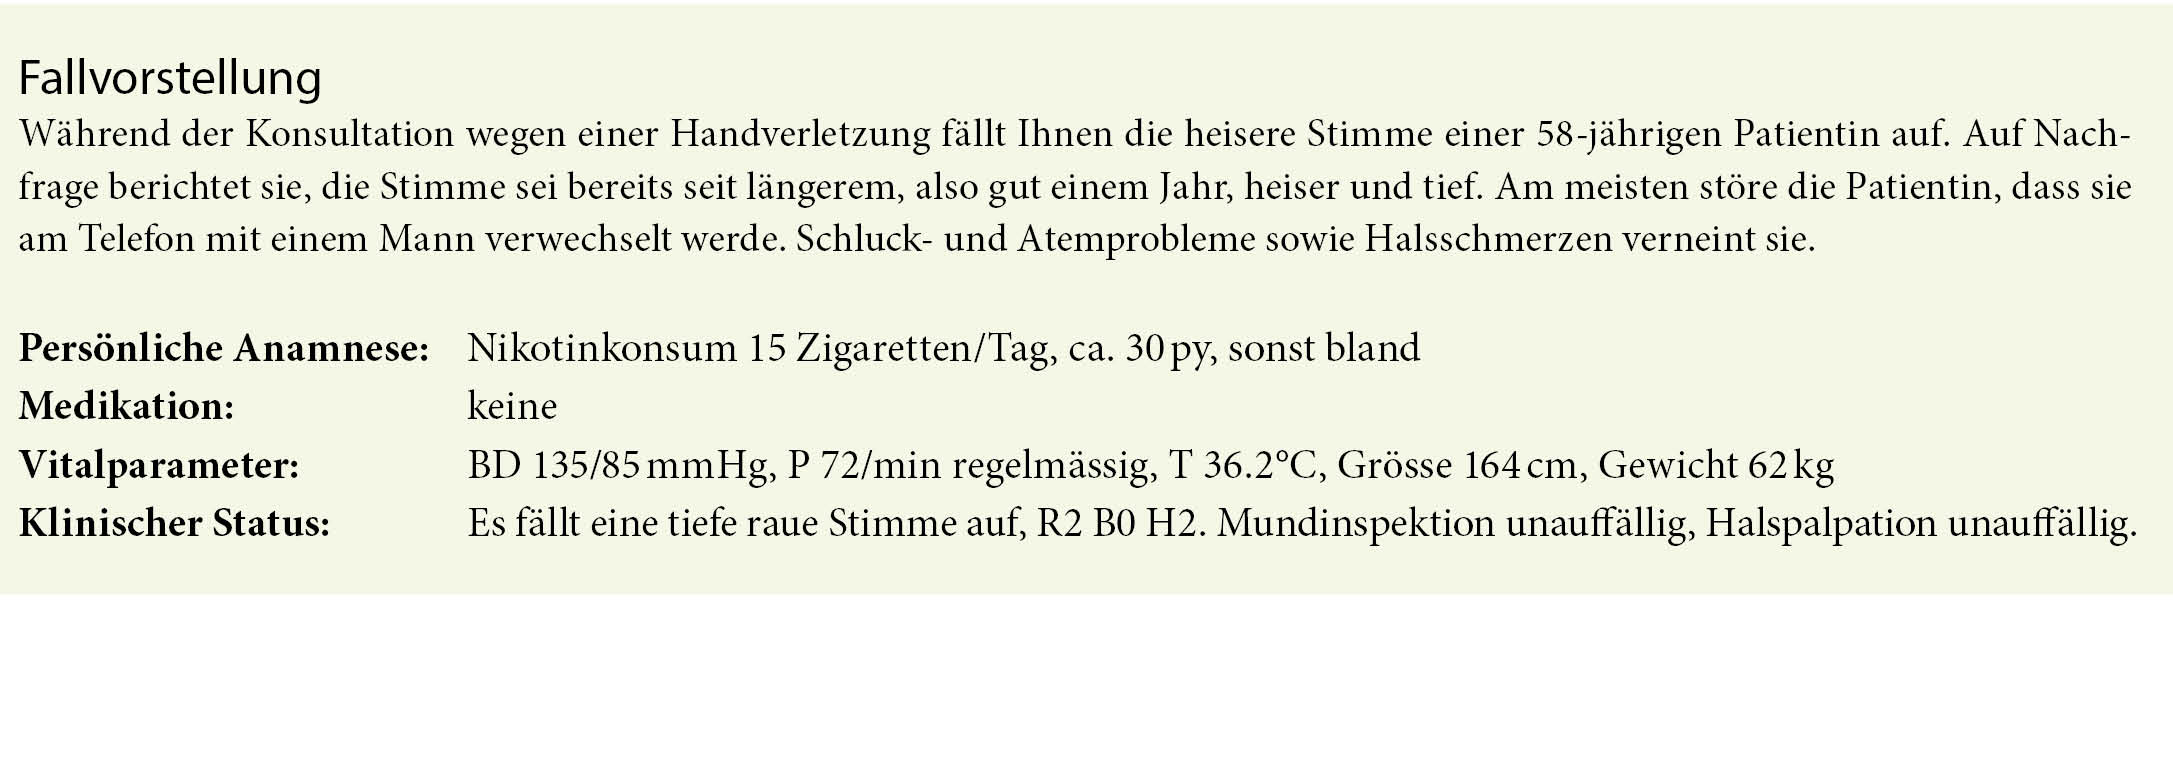

Wir haben vor uns eine 58-jährige Raucherin mit chronischer Heiserkeit, ohne weitere Symptome. Zur Beschreibung des Heiserkeitstyps wird das RBH-System benutzt (R = Rauigkeit, B = Behauchtheit, H = Heiserkeit). Dabei werden Werte von 0-3 vergeben. Eine normale Stimme wird mit R0 B0 H0 beurteilt, bei unserer Patientin ist die Stimme mit R2 B0 H2 mittelgradig rau, nicht behaucht und mittelgradig heiser.

Die Ursachen der Heiserkeit sind sehr unterschiedlich, von banalem Infekt bis zu einem malignen Tumor. Dabei kann eine Diagnose rein anhand des akustischen Befundes der Stimme nicht gestellt werden. Man kann zwar anhand der Anamnese und Dauer der Heiserkeit gewisse Vermutungen anstellen, eine Laryngoskopie bei einem HNO Arzt oder Phoniater ist jedoch unerlässlich. Eine Laryngoskopie wird grundsätzlich empfohlen, wenn eine neu aufgetretene Heiserkeit länger als 3 Wochen persistiert und nicht abklingen will. Die Dringlichkeit hängt zudem von den Begleitumständen (Stridor, Hämoptoe) und den Risikofaktoren (Nikotin- und Alkoholabusus) ab.

Bei unserer Patientin mit über Monate rauer Stimme kommen am ehesten folgende Diagnosen in Frage:

Bei unserer Patientin zeigte sich folgender laryngostroboskopischer Befund:

Bei dieser glasigen und glatten Schwellung der beiden Stimmlippen kann eindeutig die Diagnose eines Reinke-Ödems gestellt werden. Typische Patienten sind rauchende und kommunikative Frauen im Alter von 50-60 Jahren. Eine maligne Entartung muss nicht befürchtet werden. Für die Prognose ist das Sistieren des Nikotinkonsums wichtig. Bei geringem Leidensdruck oder Initialstadium kann mit logopädischer Stimmtherapie und Nikotinstopp eine gewisse Besserung erreicht werden, in den meisten Fällen ist jedoch eine phonochirurgische Abtragung in einer kurzen Narkose nötig. Insbesondere ist eine Abtragung indiziert, wenn es bei grossen Ödemen bereits zur Belastungsdyspnoe kommt.